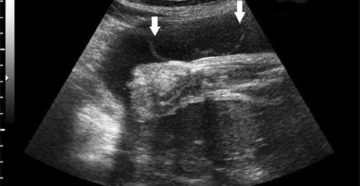

Крупнодисперсная взвесь в околоплодных водах при беременности – норма или отклонения, если мутные или прозрачные…